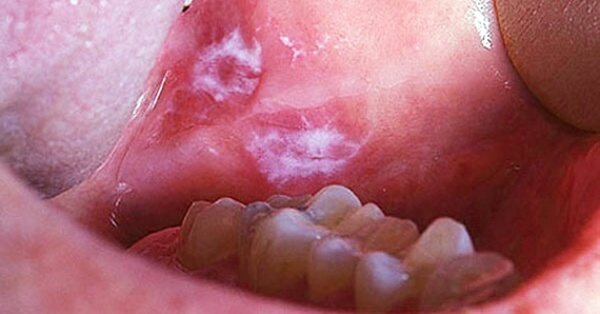

Язвочки, возникающие в ротовой полости можно отличить по 2 основным признакам. Это окрас и локализация. По цвету встречается два типа болячек:

- Белые. Окрас может меняться от молочного оттенка до светло-бежевого.

- Красные. Бывают светлыми или ярко насыщенными.

Белые в свою очередь можно подразделить на два вида:

Лейкоплакии чаще подвержены щеки, десна и язык. Причиной ее образования служит избыточное увеличение клеток. Самая высокая вероятность появления такой болячки у курильщиков. Существует риск развития рака. Кандидоз, так по-научному называется молочница, – следствие распространения грибковой дрожжевой инфекции.

В отличие от них красные язвы очень болезненны, доставляя этим много хлопот и неприятных ощущений. В основании они ярко-красного цвета. Нередко им присуща кровоточивость при прикосновении. Время восстановления может занять от 7 до 20 дней. Среди самых распространенных язв этой разновидности — язвы, сопровождающие герпес, сифилис и афтозный стоматит. Местом их локализации может выступать слизистая всей ротовой полости.